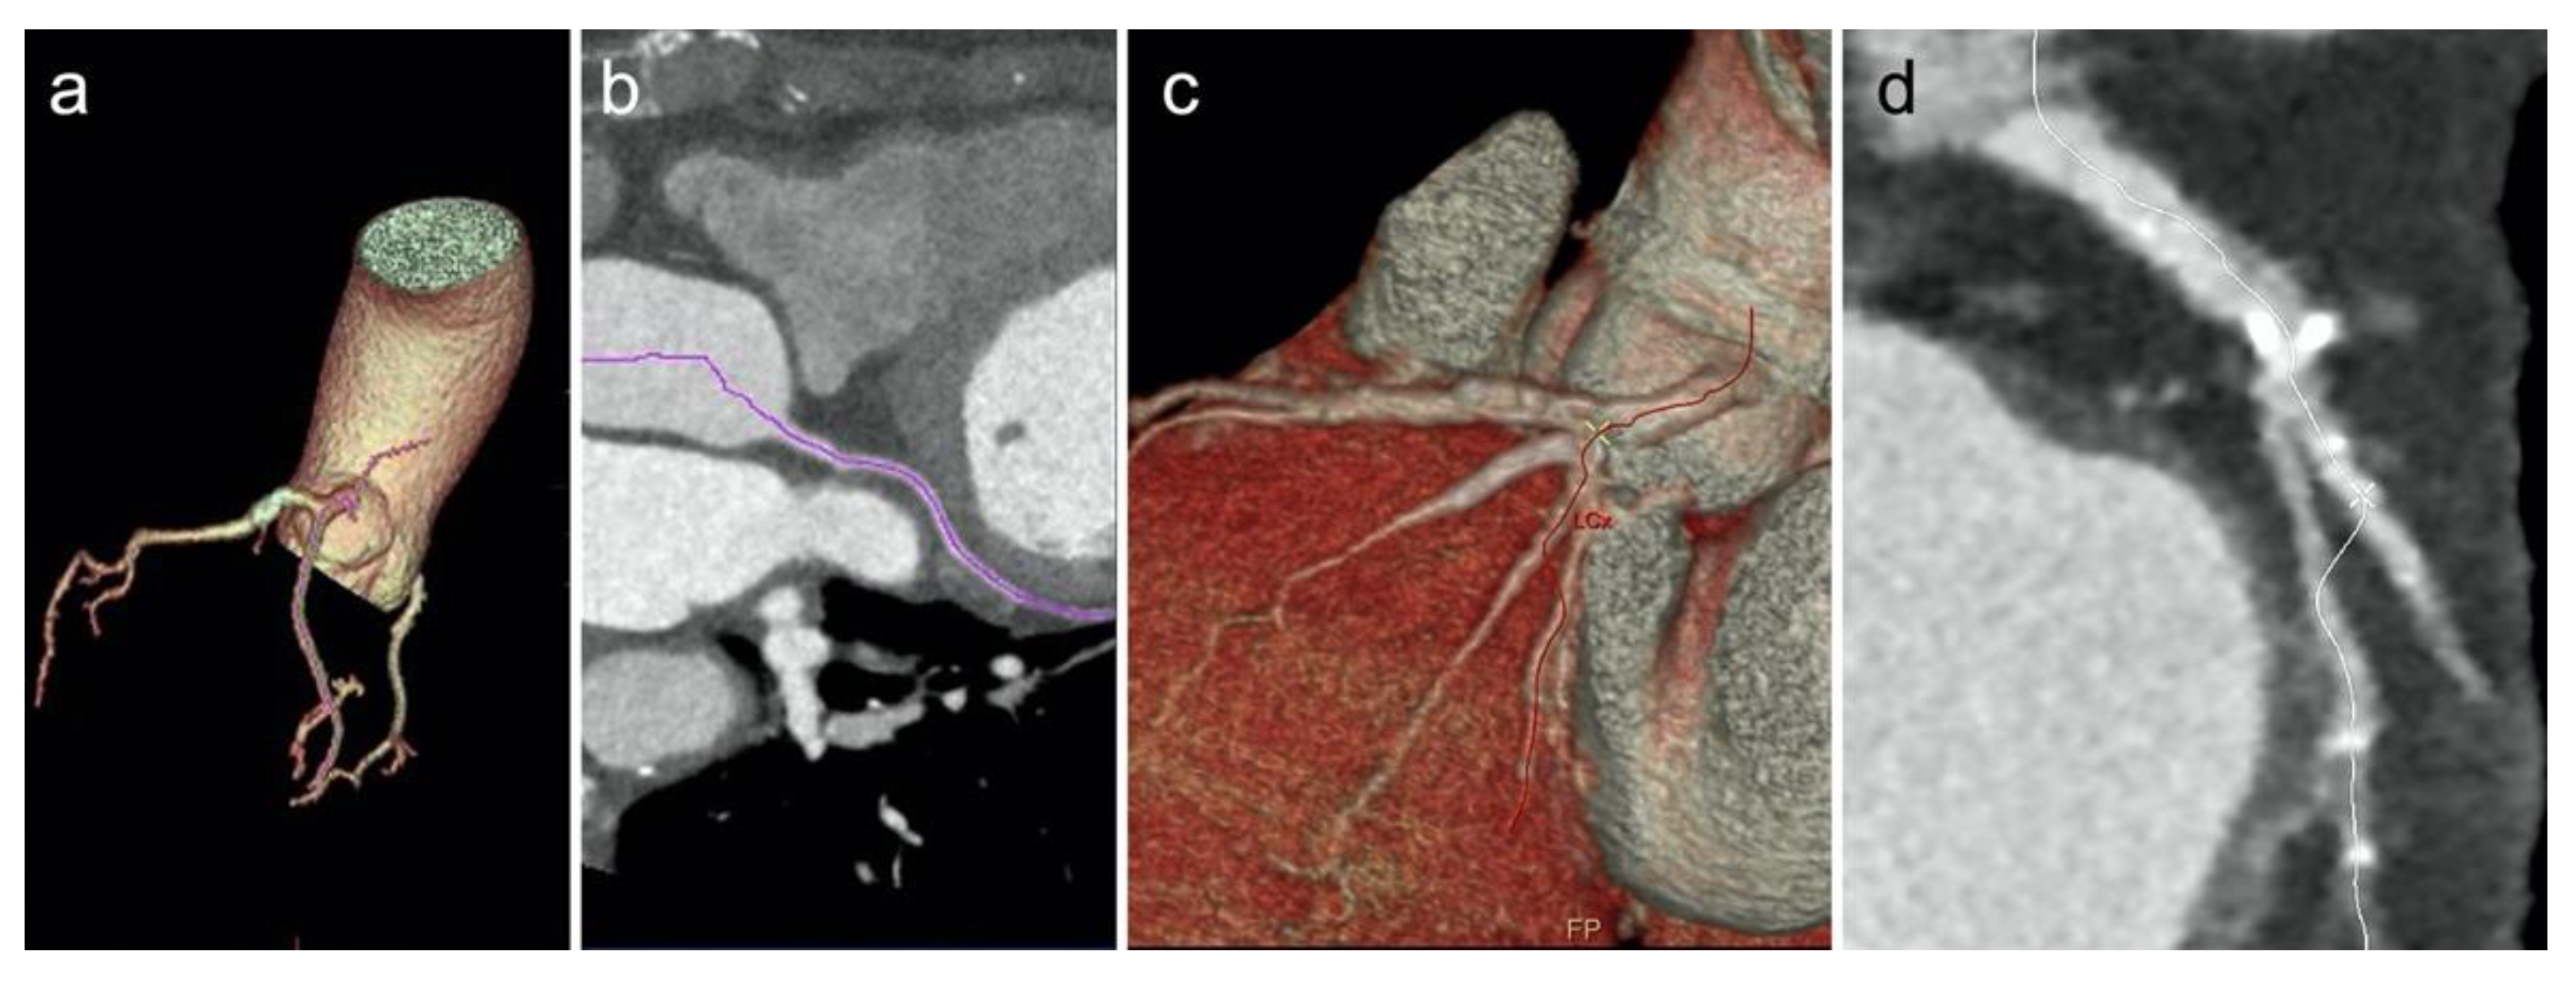

2.3. Image Post Processing—Group 1

2.5. Image Post Processing—Group 2